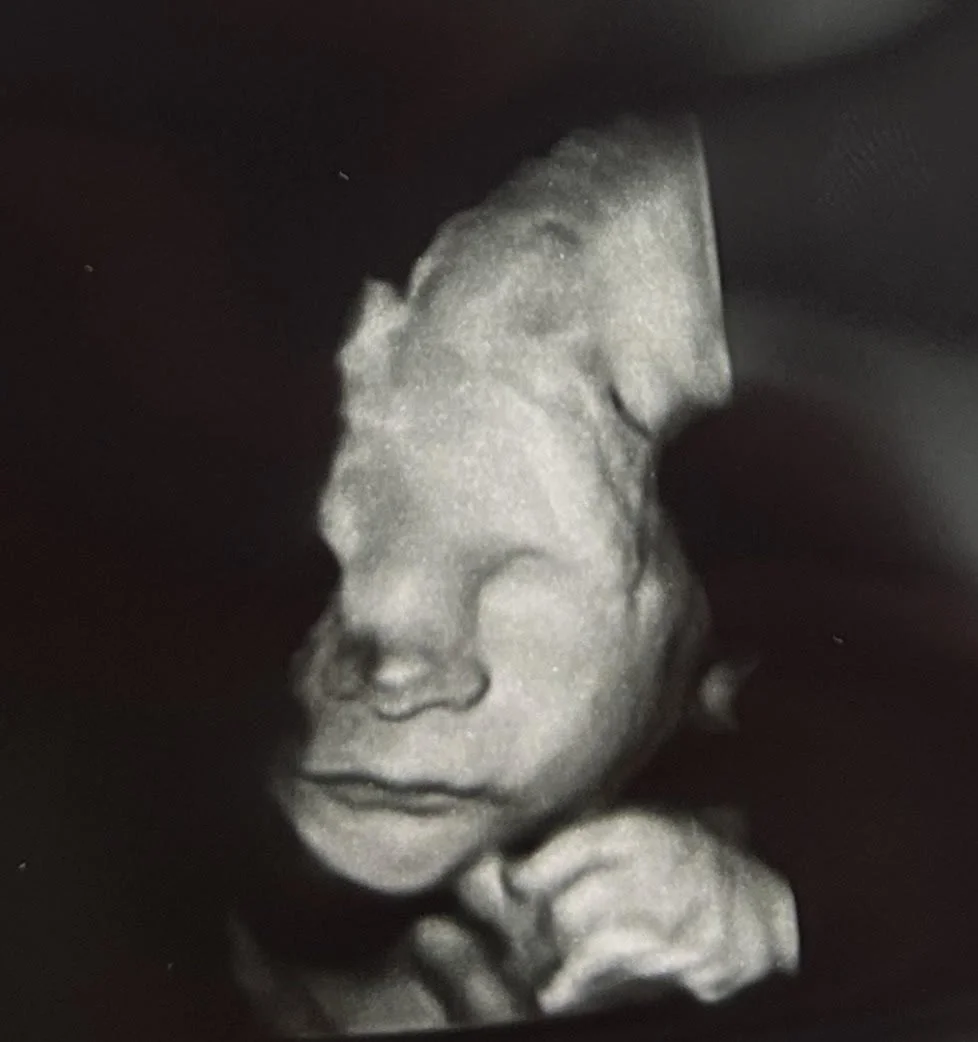

Your First Movie

A heartbeat liquid

Filming early life - don’t blink

Floating still - finally

I can’t help but love you